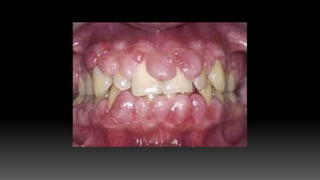

 Overgrowth usually becomes apparent in first three months of phenytoin usage.

 Starts as painless, beadlike enlargement of facial and lingual gingival margins and

interdental papilla.

 As the condition progresses, the marginal and papillary enlargements unite and develop

into massive tissue fold, covering a considerable portion of crown and may interfere with

occlusion.

 Hyperplasia is usually generalized but severe in maxillary and mandibular anterior region.

 Secondary inflammatory process may complicate gingival hyperplasia.

HISTOPATHOLOGY

 Consists of pronounce hyperplasia of epithelium and connective tissue.

 There is acanthosis of the epithelium, and elongated rete pegs extend deep

into the connective tissue, which exhibits densely arranged collagen bundles

with an increase in number of fibroblasts and new blood vessels.

IDIOPATHIC GINGIVAL ENLARGEMENT

CLINICAL FEATURES:

 It is a rare condition of undetermined cause.

 Designated by terms such as: gingivomatosis, elephantiasis, idiopathic

fibromatosis,heriditary gingival hyperplasia.

 Affects marginal, attached gingiva and interdental papilla.

 The enlargement is pink, firm and leathery and has characteristic pebbled surface .

 In severe cases, teeth are almost completely covered and the enlargement projects

into the oral vestibule.

 Secondary inflammatory changes are common at the gingival margin.